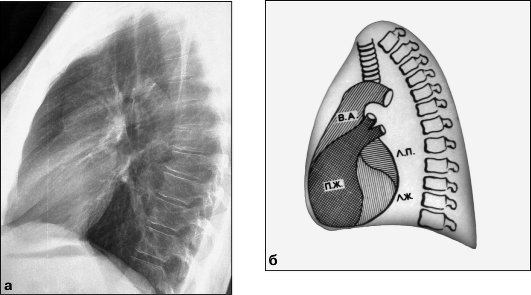

Рентгенограмма аорты

Рентгенограмма аорты 114 фотографий